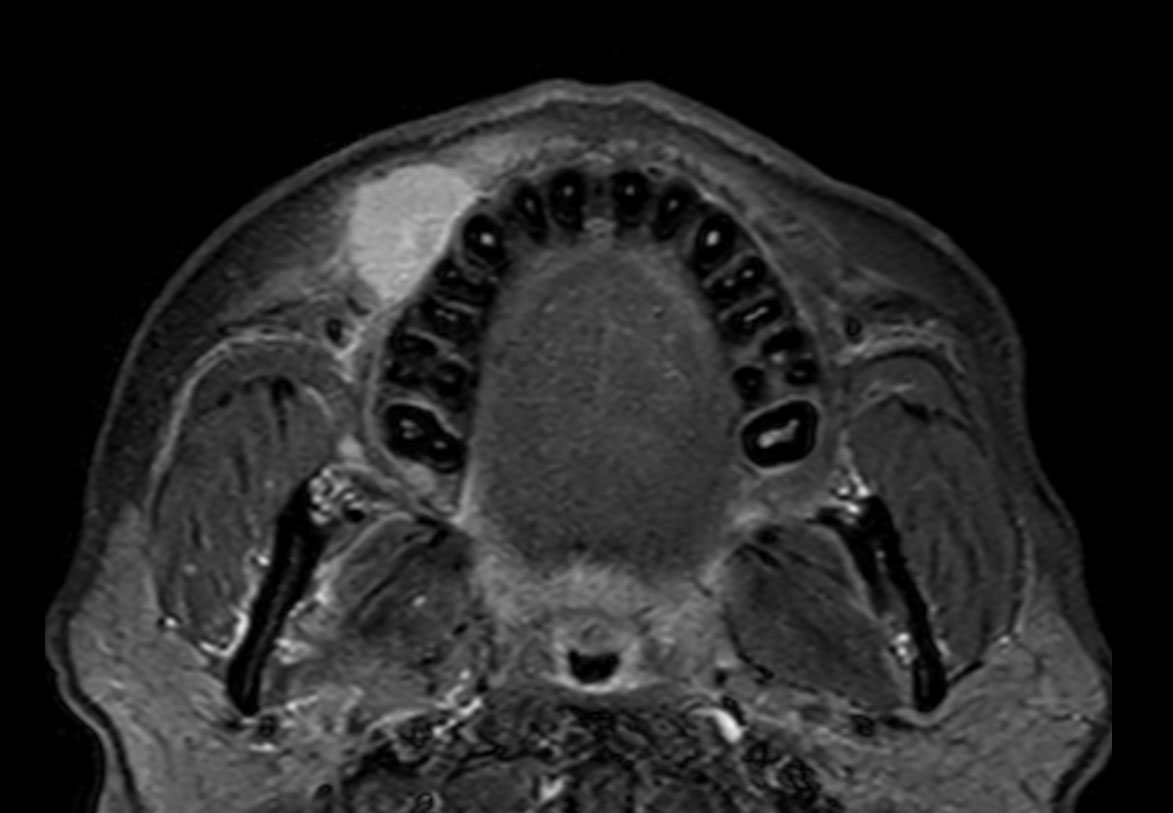

Axial T1w TSE